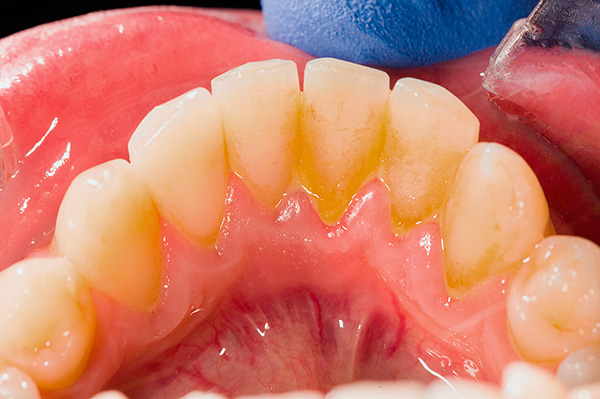

- Má higiene bucal;

A falta de higiene bucal causa acúmulo de placa e pedra nos implantes instalados, interrompendo a fixação gengival e provocando processos inflamatórios. Em tal situação, seus próprios dentes geralmente se tornam móveis no contexto da periodontite, e os implantes também "entendem" completamente.